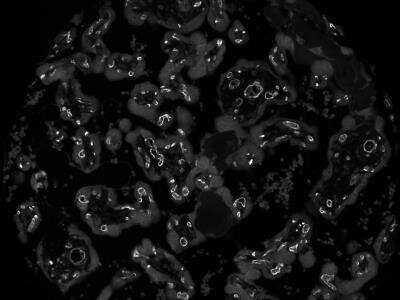

Immunohistochemistry-Paraffin: CD34 Antibody (QBEnd/10) - Azide and BSA Free [NBP2-34713]

Immunohistochemistry-Paraffin: CD34 Antibody (QBEnd/10) - Azide and BSA Free [NBP2-34713] - Formalin-paraffin human tonsil (20X) stained with CD34 MAb (QBEnd/10). Image using the standard format of this product.